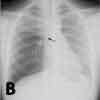

Inspiratory (A), expiratory (B), and lateral (C) chest radiographs confirmed the diagnosis of an endobronchial foreign body. Bronchoscopy revealed a blue pushpin obstructing the right bronchus intermedius and facing proximally into the large airways (D). The larynx, trachea, carina, and left main bronchus were not affected.

Chest radiographs may demonstrate air trapping, atelectasis, or consolidation and are suggestive of a radiopaque foreign body.4 In older children like this patient, chest radiographs should be obtained during inspiration and expiration. Fluoroscopy may be needed in young children. In a 10-year retrospective study, plain chest radiographs revealed a foreign body in only 23.56% of patients.5 In another retrospective study, chest radiographs were normal in 56% of children with tracheal foreign bodies.6